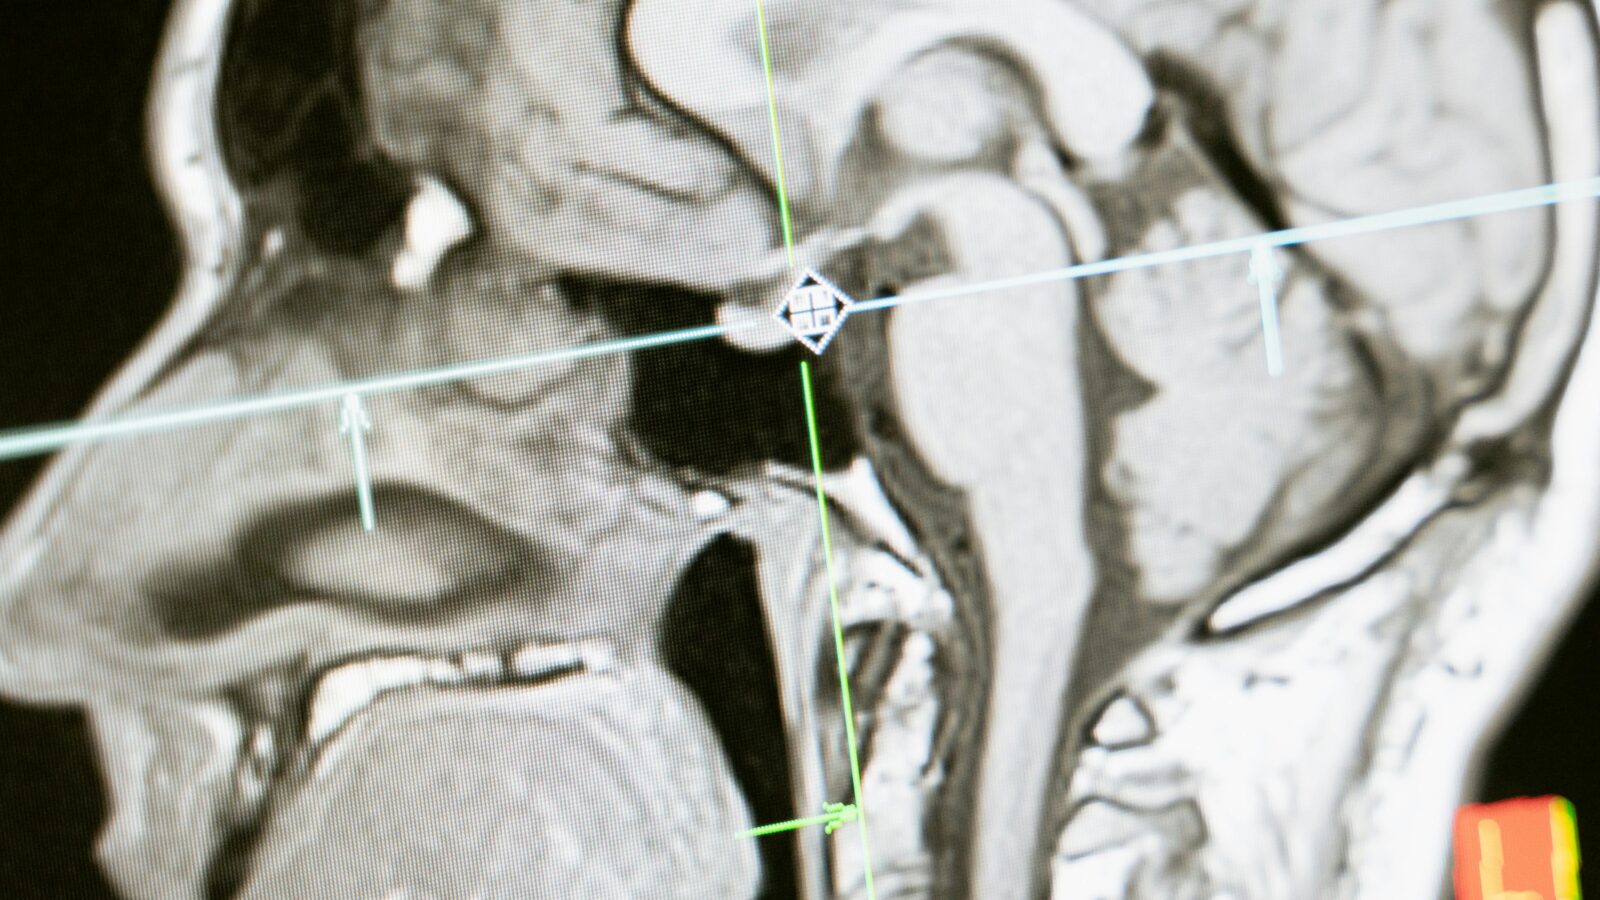

La TMS actual utiliza campos magnéticos para estimular áreas generales de la corteza cerebral. Intentar “borrar” un recuerdo específico de un evento traumático sin afectar el lenguaje, la motricidad o los recuerdos biográficos básicos es, tecnológicamente, una imposibilidad.